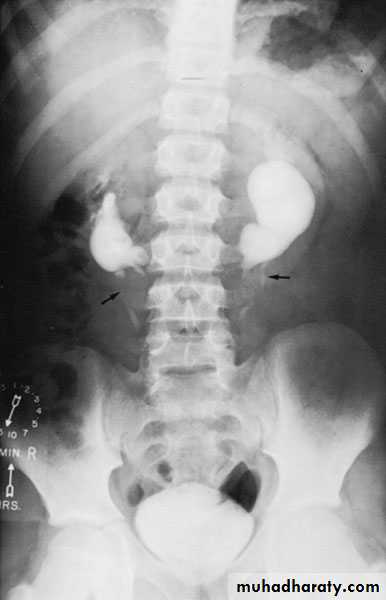

Crossed Renal Ectopia With and Without FusionHorseshoe Kidney

Found in 1:1000 necropsies and is more common in men.probably the most common of all renal fusion anomalies

The anomaly consists of two distinct renal masses lying vertically on either side of the midline and connected at their respective lower poles by a parenchymatous or fibrous isthmus that crosses the midplane of the body.

Fusion of the renal masses occurs early in embryonic life, so its ascent will be impeded by inferior mesenteric artery.

The kidneys are low located, mal rotated and pelves lie anteriorly

Symptoms

When present, they are related to complications like hydronephrosis, infection, or calculus formation

Diagnosis ultrasound, IVU, CT scan

Treatment:

Medical: pain relief and to control infectionSurgical: stone removal, PUJ stenosis correction and isthmus division in cases of operations on the aorta

Prognosis: usually they have normal life.